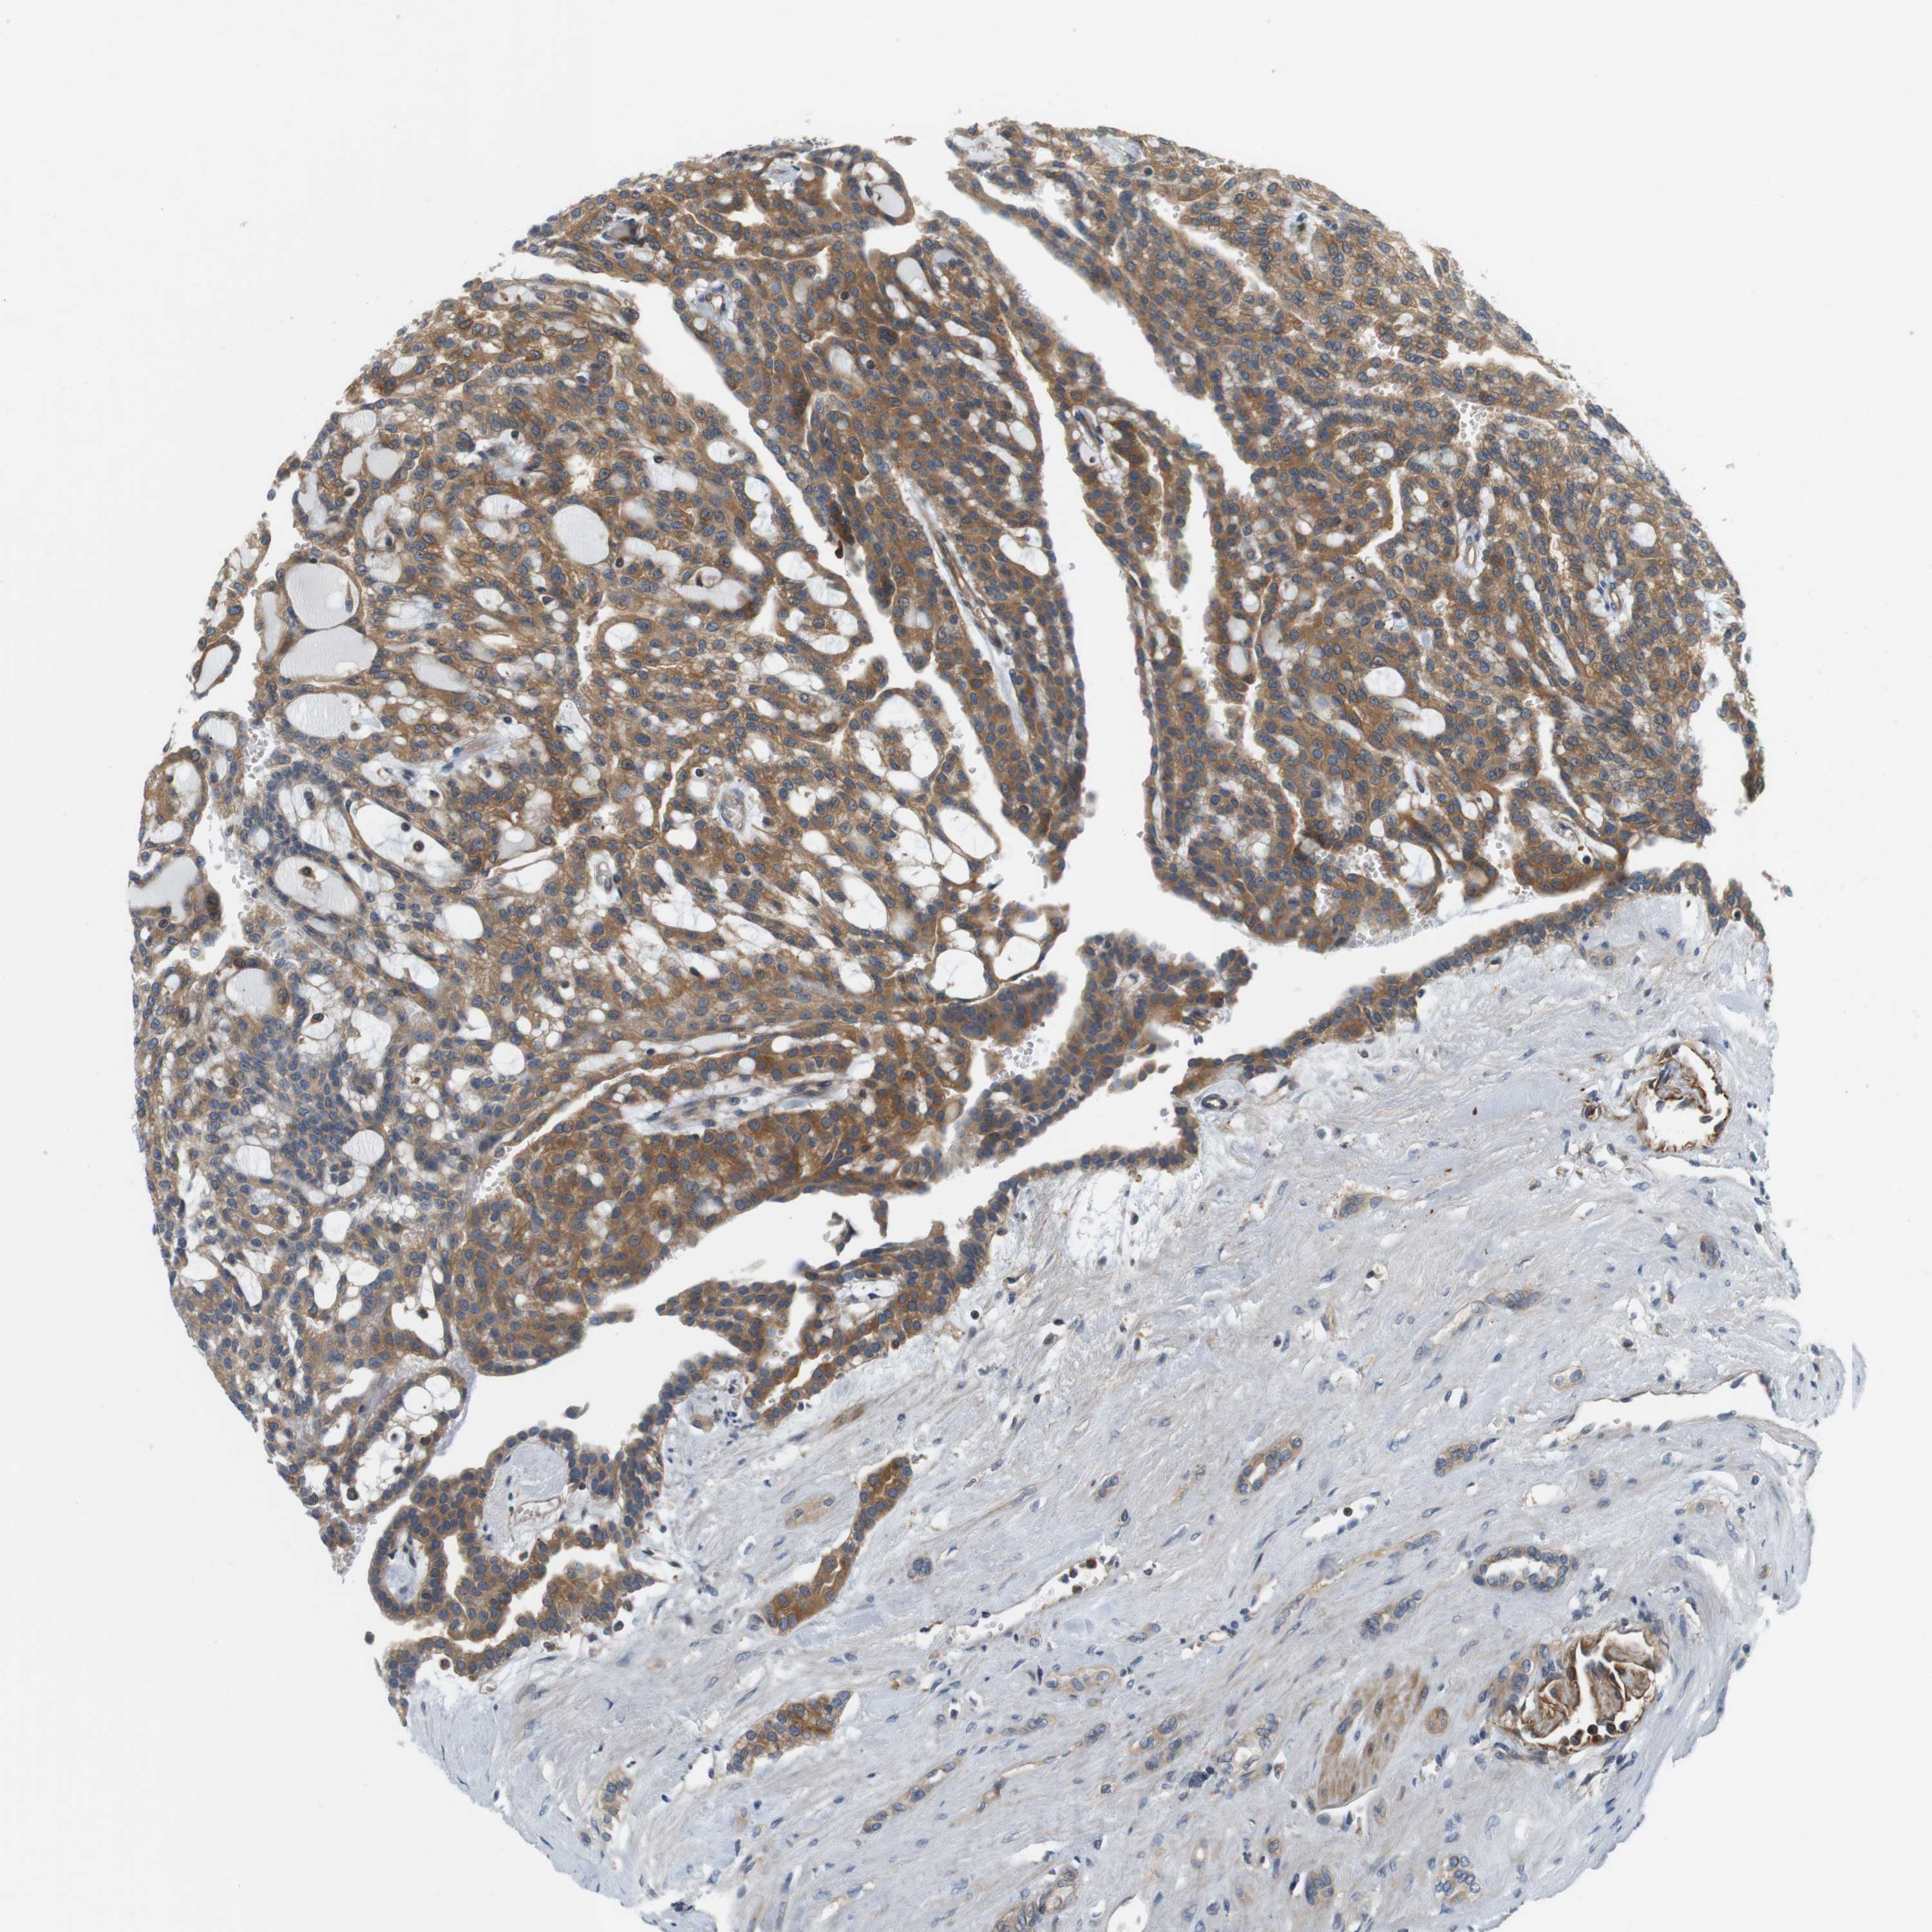

KIDNEY RENAL CLEAR CELL CARCINOMA (TCGA) - Interactive survival scatter ploti

The Survival Scatter plot shows the clinical status (i.e. dead or alive) for all individuals in the patient cohort, based on the same data that underlies the corresponding Kaplan-Meier plots. Patients that are alive at last time for follow-up are shown in blue and patients who have died during the study are shown in red.

The x-axis shows the expression levels (FPKM) of the investigated gene in the tumor tissue at the time of diagnosis. The y-axis shows the follow-up time after diagnosis (years). Both axes are complimented with kernel density curves demonstrating the data density over the axes. The top density plot shows the expression levels (FPKM) distribution among dead (red) and alive patients (blue). The right density plot shows the data density of the survived years of dead patients with high and low expression levels respectively, stratified using the cutoff indicated by the vertical dashed line through the Survival Scatter plot. This cutoff is automatically defined based on the FPKM cutoff that minimizes the p-score. The cutoff can be changed by dragging the vertical line or by entering a cutoff value in the square labeled "Current cut-off".

Under the Survival Scatter plot the p-score landscape (black curve; left axis) is shown together with dead median separation (red curve; right axis). Dead median separation is the difference in median mRNA expression between patients who have died with high and low expression, respectively. It is calculated as follows: median FPKM expression of dead patients with high expression - median FPKM expression of dead patients with low expression. This is intended to aid the user in visually exploring custom cutoffs and the associated p-scores and dead median separation.

Individual patient data is displayed and can be filtered by clicking on one or more of the category buttons on the top of the page. Categories describing expression level and patient information include: high, low, alive, dead, female, male and tumor stages. The scale of the x-axis can be toggled between linear and log-scale by clicking on the "x log" button. Mouse-over function shows TCGA ID, patient information and mRNA expression (FPKM) for each patient.

& Survival analysisi

Kaplan-Meier plots summarize results from analysis of correlation between mRNA expression level and patient survival. Patients were divided based on level of expression into one of the two groups "low" (under cut off) or "high" (over cut off). X-axis shows time for survival (years) and y-axis shows the probability of survival, where 1.0 corresponds to 100 percent.

SH3GLB1 is validated prognostic, high expression is favorable in Kidney Renal Clear Cell Carcinoma (TCGA)

Best expression cut offi

Based on the FPKM value of each gene, patients were classified into two groups and association between prognosis (survival) and gene expression (FPKM) was examined. The best expression cut-off refers the FPKM value that yields maximal difference with regard to survival between the two groups at the lowest log-rank P-value. Best expression cut-off was selected based on survival analysis .

When clicking on this number, the vertical dashed line indicating cut-off, the interactive survival plot, and the Kaplan-Meier curve will be adjusted to show results based on the best expression cut-off.

: 44.56

TCGA RNA samplesi

RNA-seq data is reported as average FPKM (number Fragments Per Kilobase of exon per Million reads), generated by the The Cancer Genome Atlas (TCGA) .

Normal distribution across the dataset is visualized with box plots, shown as median and 25th and 75th percentiles. Points are displayed as outliers if they are above or below 1.5 times the interquartile range. FPKM values of the individual samples are presented next to the box plot.

Average pTPM 64.2

Number of samples 521